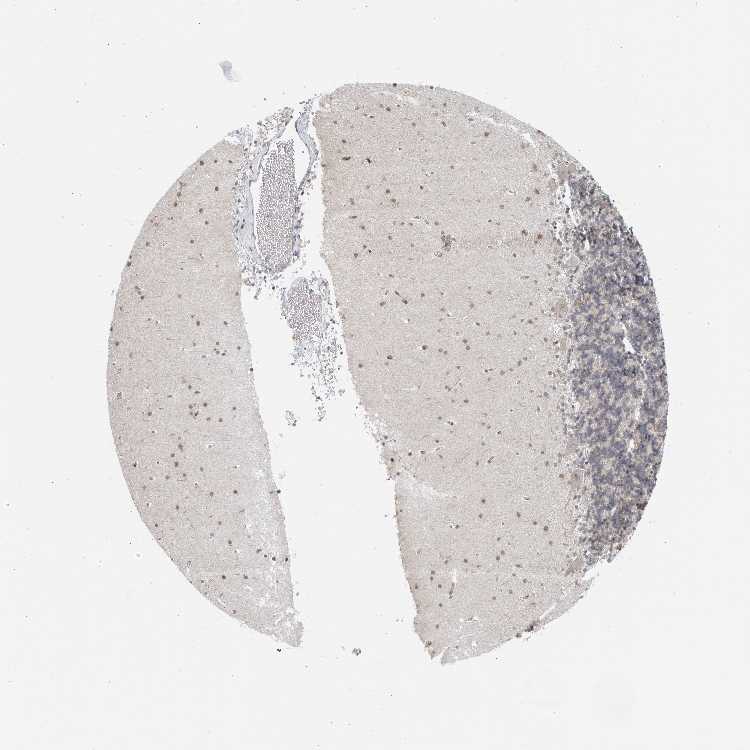

CEREBELLUM - Antibody stainingi

Antibody staining in the annotated cell types in the current human tissue is reported as not detected, low, medium, or high, based on conventional immunohistochemistry profiling in selected tissues. This score is based on the combination of the staining intensity and fraction of stained cells.

Each image is clickable and will lead to virtual microscopy that enables deeper exploration of all samples and also displays staining intensity scores, fraction scores and subcellular localization as well as patient and tissue information for each sample.

Antibody HPA028088Antibody HPA028631Antibody HPA030086

Purkinje cells Not detectedNot detectedLow

Cells in granular layer Not detectedNot detectedMedium

Cells in molecular layer Not detectedLowLow